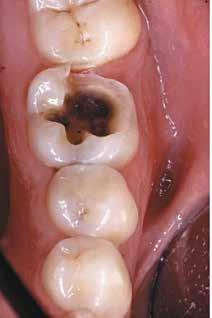

Fig. 2. Med udgangspunkt i tænder med stigende sammenbrud af en dentineksponeret carieslæsion kan et forventeligt billede af et fremadskridende mønster af ubehandlet caries fremstilles. Jo flere sammenbrudte dentinflader, desto mere åbenlæsions-topologi (A-E). I forhold til radiologisk penetrationsdybde tæt på pulpa vil dybdelæsioner med synlig radioopak zone mellem læsion og pulpa have lav risiko for bakterier i pulpa (F) overfor ekstremt dybe læsioner, der har radiologisk kontakt til pulpa (G). Læsionens topologi har konsekvenser for vækstbetingelserne af en biofilm. ”Lukkede” dentin-caries-læsioner har tydelig biofilmakkumulering, blød gullig/lysbrun dentinoverflade og med et underminerende spredningsmønster langs med emalje-dentin-grænsen (H). I modsætning til ”åbne” læsioner, der er mere mørkfarvede uden nævneværdig akkumulering af biofilm (I). (Med tilladelse fra (16) og Wiley).

Fig. 2. A picture of a progressing pattern of one untreated caries lesion is expected based on teeth with increasing break-down of a dentine-exposed carious lesion, and this is confirmed in this figure. The more surfaces that are involved in a cavity the more “open” topology (A-E). In relation to the radiological penetration depth close to the pulp, deep lesions with a visible radiopaque zone between the lesion and the pulp will have a low risk of bacteria in the pulp (F) compared to extremely deep lesions that have radiological contact with the pulp (G). The topology of the lesion has consequences for the growth conditions of a biofilm. "Closed" dentin caries lesions have clear signs of biofilm accumulation, a soft yellowish/light brown dentin surface and with an undermining spreading pattern along the enamel-dentine border (H). In contrast to “open” lesions that are darker in colour without appreciable accumulation of biofilm (I). (With permission from (16) and Wiley).

filmen, og deres produktion af organiske syrer fører til demineralisering af de hårde tandvæv (emalje, dentin og cement). I begyndelsen vil demineraliseringen ikke føre til en egentlig kavitetsdannelse på tandoverfladen til trods for, at der både er mineraltab i emalje og dentin, men den gradvise demineralisering over tid vil ubehandlet kunne svække emaljelæsionens centrale dele. De mastikatoriske kræfter vil føre til dannelse af mikrokaviteter efterfulgt af egentlige kliniske kaviteter (Fig. 1). På sigt fører dette til, at den demineraliserede emaljelæsion bryder sammen og eksponerer den underliggende demineraliserede dentin. På dette tidspunkt siges læsionen at være kaviteret eller klinisk dentin-eksponeret. Hvorvidt en carieslæsion progredierer eller ej, beskrives konceptuelt med begrebet “cariesaktivitet” eller “læsionsaktivitet”. Begrebet dækker både over, hvorvidt der ses akkumulering af biofilm på overfladen af carieslæsionen, samt hvorvidt man klinisk kan se tegn på aktiv produktion af syre i den akkumulerede biofilm. Cariesaktivitet kan tillige bekræftes radiologisk (Fig. 1A og B). En aktiv carieslæsion er kort sagt dækket af en cariogen biofilm og vil derfor progrediere med øget penetrationsdybde af læsionen til følge, hvorimod en inaktiv carieslæsion ikke på samme måde har en overfladebiofilm og heller ikke vil udvikle sig med særlig stor hastighed (1). Om end inaktive carieslæsioner vil kunne aktiveres på ny, er den nuværende kliniske forståelse, at intervention ikke umiddelbart er nødvendigt eller i det mindste kan begrænses kraftigt i tilfælde af inaktive læsioner. Muligheden for akkumulering af biofilm, selv i en kaviteret carieslæsion, afhænger til en vis grad af, hvorvidt carieslæsionen kan beskrives som værende “lukket” eller “åben” (16). Jo færre tandflader der er involveret i en kaviteret carieslæsion, jo mere “lukket” eller “skålformet” vil læsionens topologi være (Fig. 2A-E), hvilket tillader akkumulering af biofilm i læsionsmiljøet. En carieslæsion med et lukket læsionsmiljø vil derfor som oftest være en aktiv læsion, hvorimod åbne carieslæsioner ikke vil kunne akkumulere biofilm i samme omfang og derfor vil forventes at have en tilsvarende lavere progressionshastighed til trods for et ellers fremskredent stadie. Aktive dentin-caries-læsioner dækket af biofilm vil klinisk kunne beskrives som værende hvidlige/gullige/lysbrune (Fig. 2H-I), og den carierede dentin vil være blød og ikke mindst fugtig eller våd. I modsætning hertil fremstår inaktive læsioner mørkfarvede, læderagtige og uden nævneværdig akkumulation af biofilm (Fig. 2I). Desuden udviser inaktive carieslæsioner ikke samme grad af fugtighed (22). Progression og spredning af en aktiv carieslæsion vil ikke blot føre til øget penetrationsdybde, men også lede til underminering af emaljen. Dette kan ses som retrograd demineralisering (Fig. 2H). I takt med at carieslæsionen gradvist underminerer emaljen, vil emaljen på et tidspunkt være så u-understøttet, at den almindelige tyggefunktion vil føre til, at emaljen knækker af. Et resultat af dette er, at carieslæsionen bliver mere “åben”. I den nu relativt mere åbne carieslæsion vil akkumulering af biofilm ikke kunne finde sted i samme omfang som før (Fig. 2I), og carieslæsionens progressionshastighed eller aktivitet vil mindskes eller stoppe fuldstændigt (16,23). Dette dynamiske skift imellem aktivitet og inaktivitet kan ses ved både dybe og mindre dybe carieslæsioner og danner fra et klinisk perspektiv